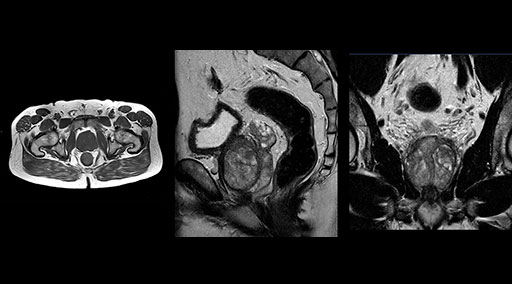

“Without using an endorectal coil we do our prostate MR at 0.5 mm resolution, following the European society of urology protocol [1]. For certain joints we use a virtual arthroscopy protocol with 1 mm pixel size and 2 mm slice thickness. Ingenia really excels in our neurography, brachial plexus and prostate scans. Our neurologists insist on using our 3.0T for those,” Dr. Kaakaji adds.

Patrick Duffy BS, RT (R) MR is Lead Technologist at DMG. “We are getting phenomenal image quality on all types of exams,” he says. “Our MSK is stellar, and so is our abdominal work. Ingenia excels at feet, hands and fingers. We do enterographies with great results. With the combination of the 3.0T magnet and the digital coils, we are able to scan prostates without an endorectal coil while still obtaining high quality results. This is a comforting experience for our male patients. We scan many obese patients, and the Ingenia does a tremendous job because of MultiTransmit, which reduces dielectric shading for more confident diagnosis. Our technologists really enjoy scanning on the Ingenia. We also have ordering physicians who specifically want their patients scanned on the Ingenia because of the results of our imaging.